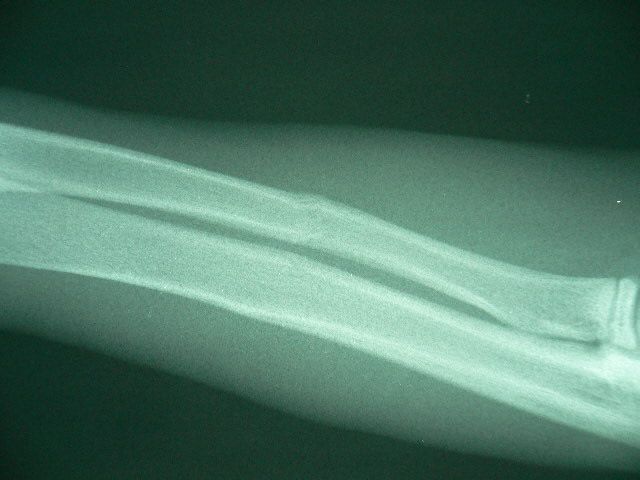

●一か月後

受傷後一か月目にレントゲンを撮影しました。体も一回り大きくなって、全く足を骨折したことなどとっくに忘れています。「いんちゃん!くれぐれも気をつけてね、あまり高いところから飛ぶんじゃねーぞ!」